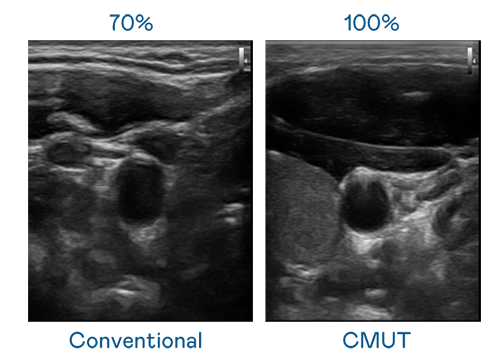

CMUT 技术是一种用电容式微机电元件来产生超音波讯号的技术。与传统 PZT 压电式技术相比,CMUT 频宽增加 30%,更宽频的超音波讯号让影像解析度大幅提升,是实现高影像品质医疗超音波扫描、促进精准医疗发展的关键技术。

超音波影像的解析度高低,首先取决于探头能发出的讯号频宽。尊龙人生就是博首页登录 CMUT 可提供高清晰的超音波讯号,提供高频宽、高灵敏度、影像纹理细节更高的超音波影像,协助医护人员缩短影像判读时间及利用精准的医疗影像进行诊断。